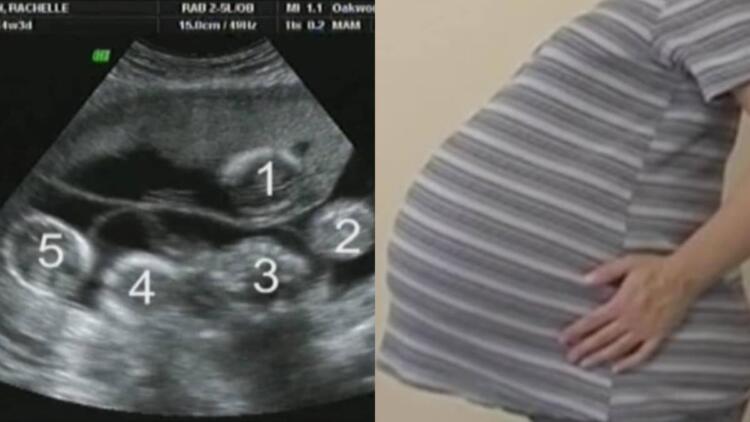

Η ιστορία θα μπορούσε να είχε τελειώσει εδώ, αλλά δεν ήταν γραφτό. Την επόμενη φορά που πήγαν στον γιατρό, υπήρχαν ακόμα δύο παλμοί. Ένας, δύο – δίδυμα. Όμως, υπήρχε και τρίτος… και τέταρτος. Και δεν σταματούσε εκεί. Υπήρχαν 5 παλμοί, 5 μωρά στην κοιλιά της. Η Rachelle ήταν έγκυος σε πεντάδυμα, κάτι συμβαίνει μερικές φορές σε άτομα που κάνουν θεραπείες γονιμότητας.

Ήρθαν αντιμέτωποι με μια πολύ δύσκολη απόφαση, αλλά στο τέλος ο Jayson και η Rachelle αποφάσισαν να συνεχίσουν την επικίνδυνη εγκυμοσύνη, ελπίζοντας ότι τα μωρά θα τα κατάφερναν. Κόντρα σε όλες τις πιθανότητες, τα μωρά αναπτύχθηκαν μια χαρά! Πόσο τυχεροί ήταν που η ιστορία πήρε αυτή την τροπή. Η κοιλιά της Rachelle μεγάλωνε όλο και περισσότερο. Εδώ είναι στις 33 εβδομάδες: